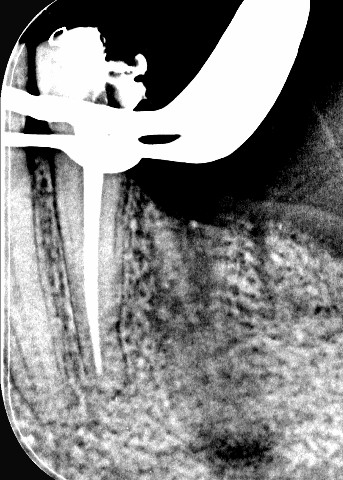

Root canal treatment with crown restoration

Complex endodontic case